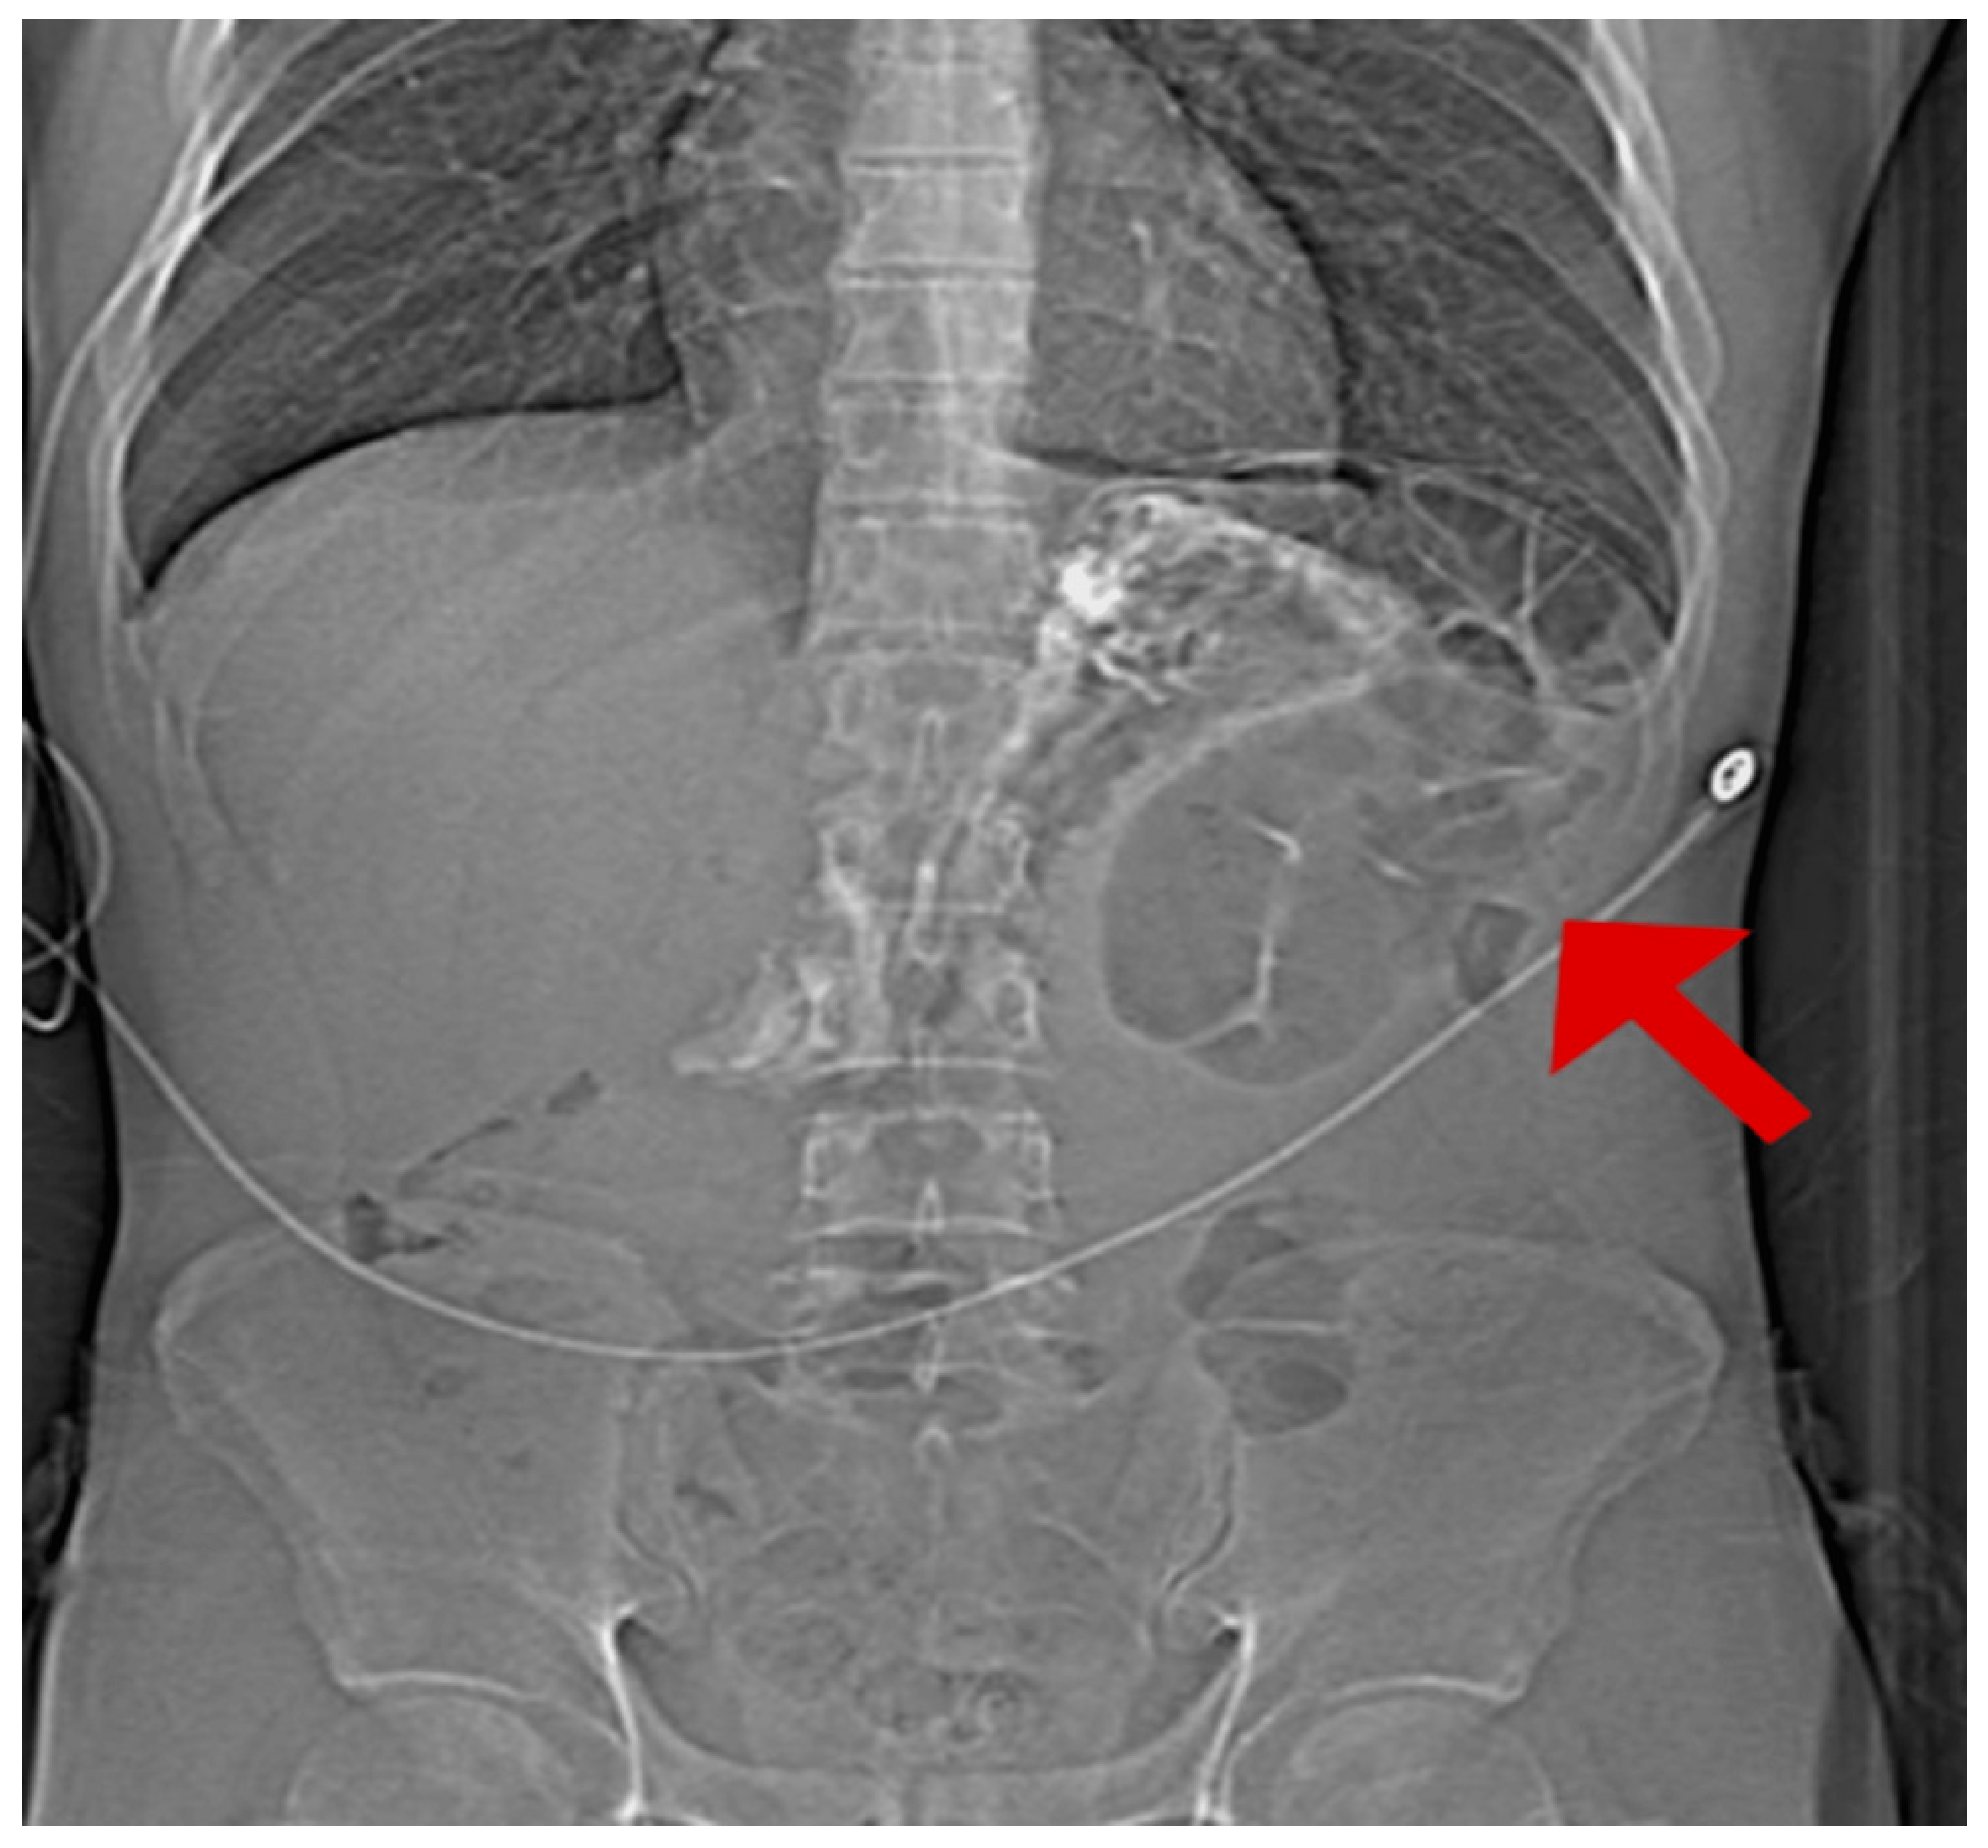

The diagnosis was established through imaging and laboratory studies. The initial chest radiograph showed an air–fluid level above the left hemidiaphragm, followed by a non-contrast CT (Figure 6).

Figure 6. Pre-operative CT survey scan demonstrating anatomical relationship between diaphragmatic defect (red arrow) and herniated abdominal contents. The measurement marker indicates the size of the defect.